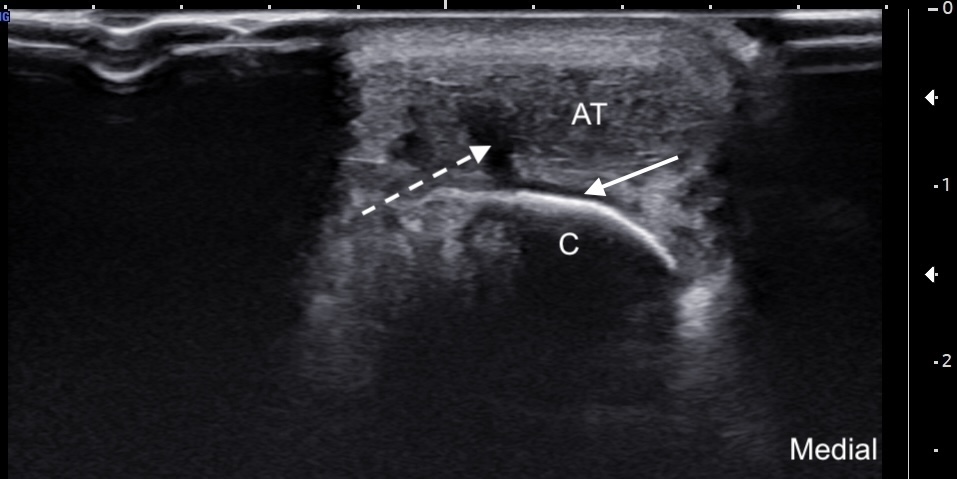

Labeled short-axis ultrasound image of the insertional Achilles tendon, a few millimeters distal to the superior edge of the calcaneus, demonstrating findings similar to those in Figure 4, with the addition of a clearly visible subcortical cyst.

Labels: AT: Achilles tendon, C: calcaneus, solid arrow: subcortical cyst, dashed arrow: partial tear.

Unlabeled short-axis ultrasound image of the insertional Achilles tendon, a few millimeters distal to the superior edge of the calcaneus, demonstrating findings similar to those in Figure 4, with the addition of a clearly visible subcortical cyst.

Image Interpretation: Chronic insertional and pre-insertional Achilles tendinosis associated with a Haglund's deformity. There is subcortical cystic change at the level of the Haglund deformity, consistent with chronic Achilles tendon pathology. Partial tearing of the deep fibers of the Achilles tendon is noted adjacent to the bony prominence. A mild retrocalcaneal bursal effusion is also present.